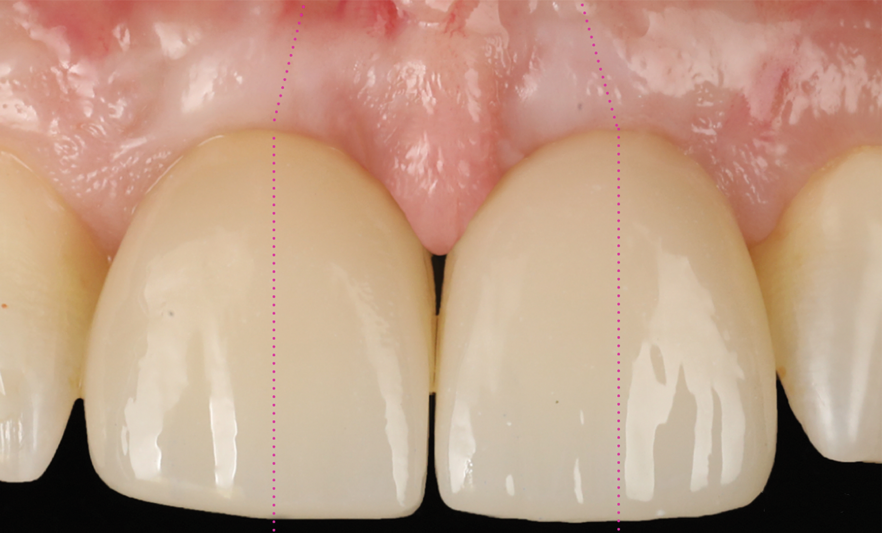

A 46-year-old systemically and periodontally healthy woman presented to the Graduate Periodontics Clinic at the University of Michigan School of Dentistry with the chief complaint of poor esthetics of her smile due to two dental implants (Nos. 8 and 9) showing their metal components (Figure 1). The patient reported that the implants had been placed 15 to 20 years previously after an accident. Clinical examination revealed that the implants had probing depths within 3 mm (facial probing depth of 3-2-3 mm for implant No. 8 and 2-2-2 mm for implant No. 9), no bleeding on probing, and no suppuration; the implants were therefore diagnosed as healthy (Figure 1 and Figure 2). The papilla between the two implants was deficient on the buccal aspect. The implants were buccally positioned, and a substantial lack of soft-tissue volume was noted.

Fig 1. Clinical view at presentation.

Figure 1

Fig 15. Clinical comparison of the volumetric gain obtained with the intervention, frontal views. Fig 15: Frontal view at baseline. Fig 16: Frontal view at 1-year post-treatment.

Figure 15

Fig 16. Clinical comparison of the volumetric gain obtained with the intervention, frontal views. Fig 15: Frontal view at baseline. Fig 16: Frontal view at 1-year post-treatment.

Figure 16